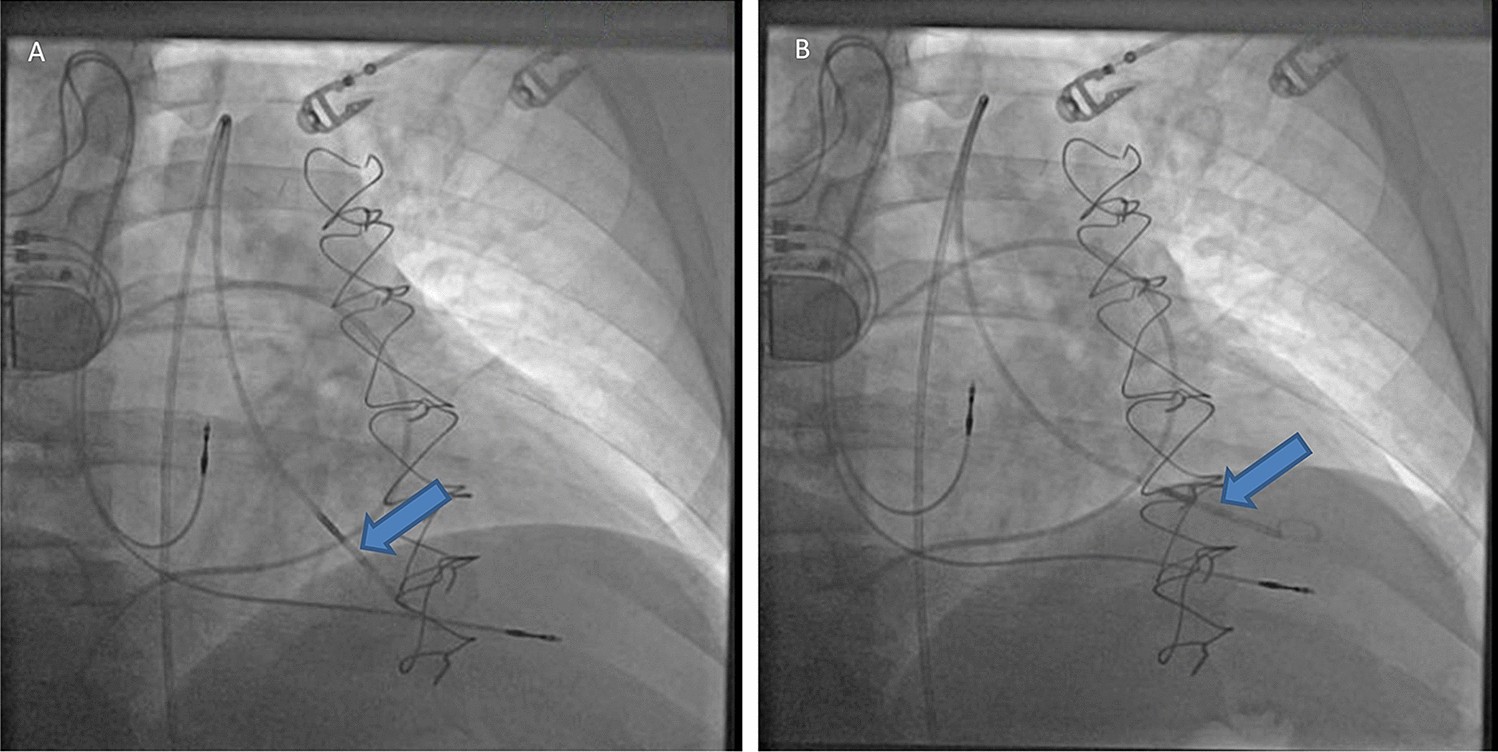

Figure 1

Representative fluoroscopy images showing the 7-French conductance catheter (Blue arrow): (A) Prior to alignment with the long axis of the left ventricle and (B) After alignment with the long axis of the left ventricle, and with catheter tip placed in left ventricular apex. Patient has dual chamber pacemaker with right atrial and right ventricular leads in the corresponding chambers. The pulmonary artery catheter is already advanced into the pulmonary artery.